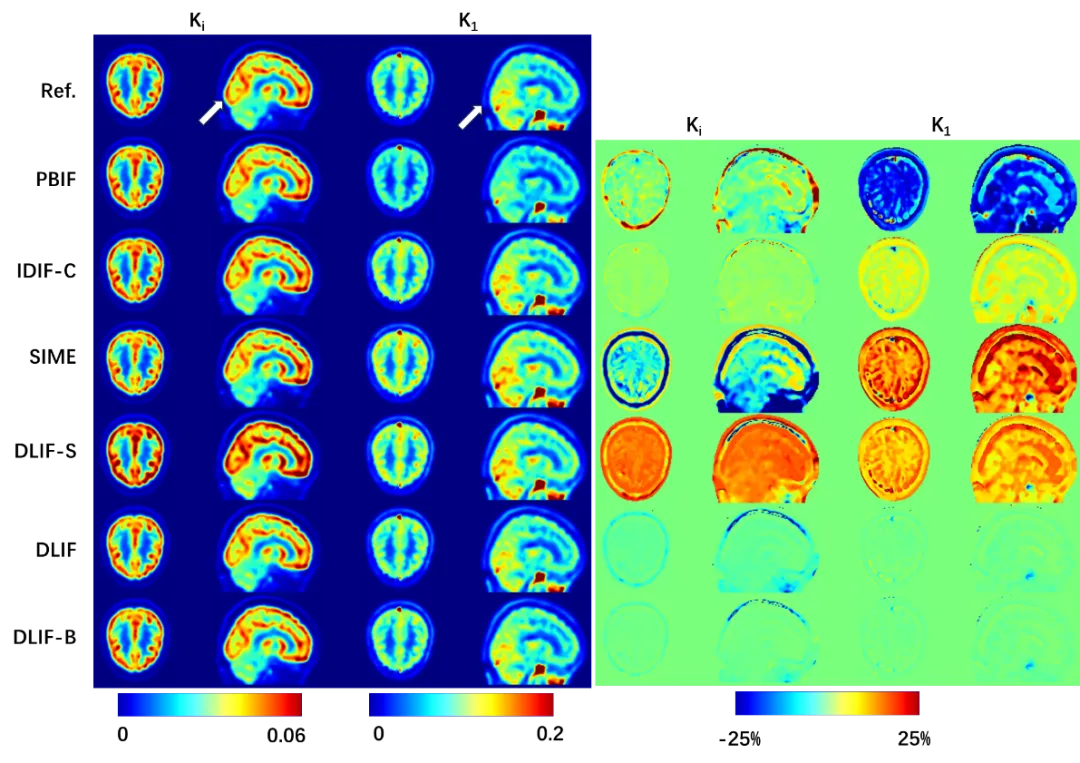

从视觉和定量两个方面来看,参数图像也与参考图像高度吻合(图3)。这些结果证实了无创且准确地估计血流输入函数的可行性,该方法适用于常规的短视野或专用脑部扫描PET系统,并且无需进行部分容积校正。顺利获得精准计算取得的全局灌注、净流入、净代谢和其他微观参数,有助于有助于在广泛的神经和精神疾病中大脑代谢功能的研究,进而辅助制定更有效的治疗策略。

图3 展示了使用不同方法估计的输入函数所计算的K1/Ki图像(左)。可以观察到,使用所提出的方法(DLIF)估计的参数图像与参考图像最为接近,且误差值范围最小(右)。